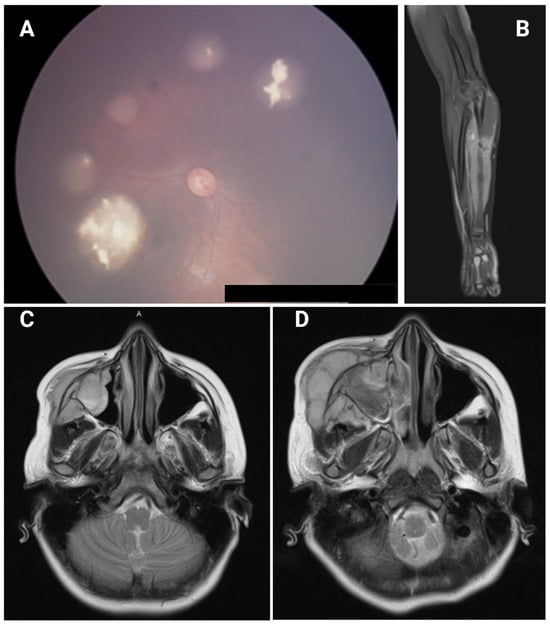

| F | 3 m | B | − | En, QT | 5 y | Sarcoma | Left ulna | 9 y | EWS | c.306T>A (p.Cys102*) | Present case |